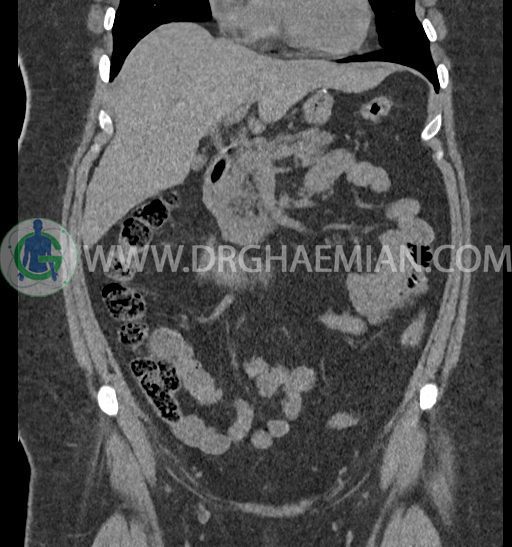

سی تی اسکن شکم و لگن با استفاده از اشعات ایکس تصاویر عرضی از ناحیه شکم و لگن ایجاد میکند. در این کیس کلیه نعل اسبی و سنگ کلیه مشاهده می شود.

در سی تی اسکن اسپیرال شکم و لگن بدون کنتراست (مولتی دیدکتور 16 با مقاطع ظریف و بازسازی های ساژیتال و کرونال) :

ضایعهای در کبد، کیسه صفرا، مجاری صفراوی، طحال، پانکراس و آدرنالها مشهود نیست.

مایع آزاد در حفره شکم و لگن رویت نمی شود.

توده، کیست و collection مشهود نیست.